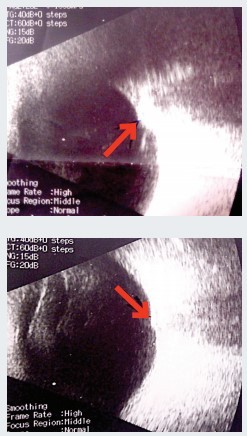

Эхоскопия. ОD — умеренная деструкция стекловидного тела, задняя гиалоидная мембрана (ЗГМ) частично отслоена, оболочки прилежат, в ДЗН гиперэхогенное включение (друзы?). OS — умеренная деструкция стекловидного тела, ЗГМ частично отслоена, оболочки прилежат, в ДЗН гиперэхогенное включение, ДЗН проминирует в стекловидное тело (см. рис. 1).

Осмотр глазного дна с фундус-линзой. OS — в основании ДЗН округлое проминирующее пигментированное (меланоцитома?) образование, границы и ткань ДЗН не определяются, мелкая капиллярная сеть по поверхности ДЗН, гиперпапиллярно отек нейроэпителия сетчатки (НЭС). Окклюзия артерий по верхневисочной и носовой аркадам, в зоне верхневисочной и верхненосовой аркад молочно-белый отек сетчатки с захватом верхней части фовеа. Сетчатка прилежит (см. рис. 2). Лазерная коагуляция не показана. Рекомендована консультация онкоофтальмолога.